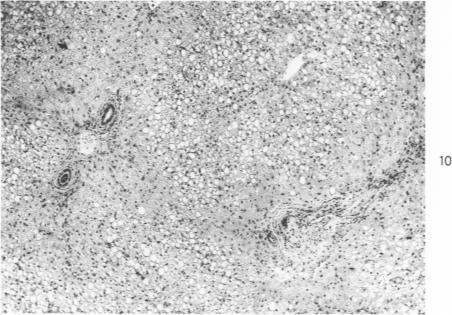

Volk B W, Lazarus S S

Am J Pathol. 1960 Aug;37(2):121-35.